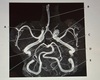

1. Which arrow points to the basilar artery? 2. Which arrow points to the anterior cerebral artery? 3. Which arrow points to the middle cerebral artery? 4. Which arrow points to the vertebral artery? 5. Which arrow points to the internal carotid artery?

1. D 2. A 3. C 4. E 5. B

1.Communicating artery? 2. Middle cerebral artery 3. Carotid siphon of internal carotid artery? 4. Anterior cerebral artery?

1. C (communicating artery) 2. A (middle cerebral artery) 3. D (carotid siphon of internal carotid artery) 4. B (anterior cerebral artery)

1. Basilar artery? 2. Anterior communicating artery? 3. Left internal carotid ?

1. Basilar artery (C) 2. Anterior communicating artery (A) 3. Left internal carotid (D)

1) vertebral artery? 2) basilar artery? 3) PICA posterior inferior cerebellar artery?

1) vertebral artery (D) 2) basilar artery (B) 3) PICA posterior inferior cerebellar artery (A)